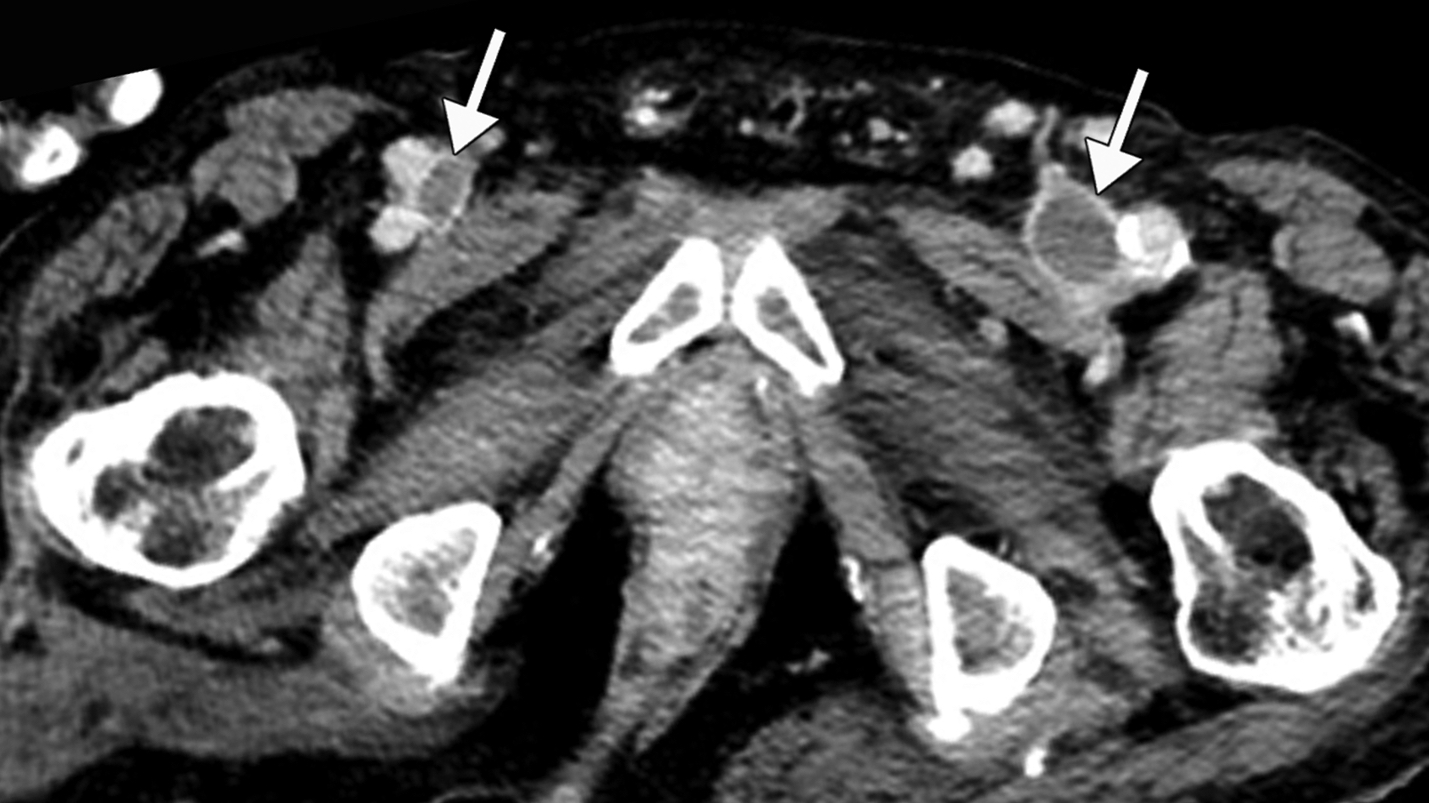

This photo gallery shows the variety of radiological presentations of COVID-19 (SARS-CoV-2) in medical imaging, including computed tomography (CT), radiograph X-rays, ultrasound, echocardiograms and magnetic resonance imaging (MRI). The radiology images show examples of typical COVID pneumonia in the lungs and the numerous complications the virus causes in the body in multiple organs, including the brain, kidneys, heart, abdomen and vascular system.

Ultrasound, especially hand-held ultrasound imaging devices, have become a primary imaging modality for novel coronavirus because of the ease to bag the device and sterilize it after use. CT and mobile X-ray systems are also used as front-line imaging systems for COVID-positive or suspected COVID patients.